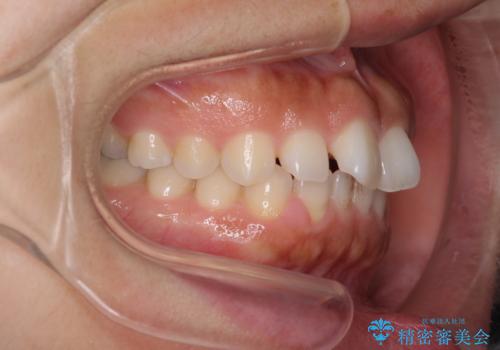

隙間の空いた前歯を閉じたい インビザライン矯正

- 前歯の隙間を気にして来院された患者様です。

隙間、捻転ともに軽微でありましたが、下顎前歯の突き上げにより隙間ができていたため、インビザラインを用いて咬み合わせを改善しながら前歯の歯列を整えていくこととしました。

当初は1年程度で終えられると思いましたが、治療途中から装着時間が短くなったり、来院間隔が長期になったりとし、結果として4年半以上の治療期間となりました。

治療途中に上顎前歯は失活してしまいましたが、変色が顕著ではないため、経過を見ていくこととなりました。